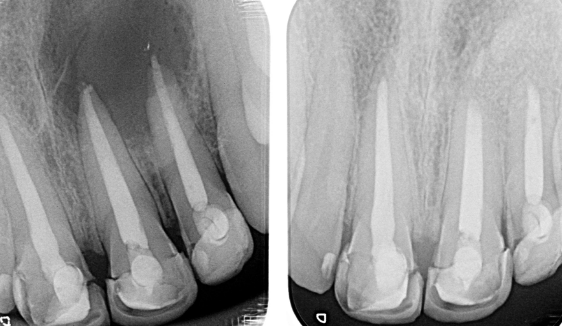

Diente fisurado tratable

Este tipo de fisura se extiende desde la superficie de masticación del diente y migra verticalmente hacia la raíz. En algunos casos, la grieta puede extenderse por debajo de la línea de las encías. Es posible que la grieta se extienda más hacia la raíz. El daño a la pulpa es común. En este caso, el tratamiento del conducto radicular suele ser necesario. Un diente roto que no se trata empeorará, lo que provocará la pérdida del diente. Por lo tanto, la detección temprana es esencial.